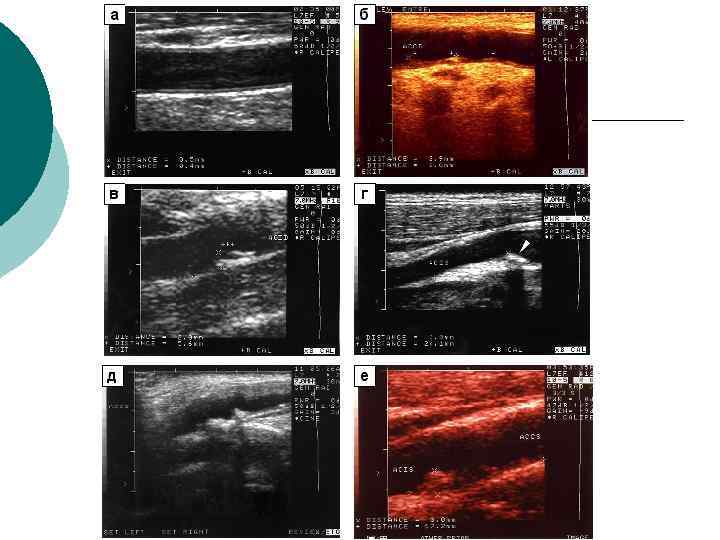

Диагностическая информативность ¡ ¡ ¡ Размеры артерий и вен; Скорости и характер движения крови; Толщина комплекса интима-медия (в норме – до 0, 8 мм в ОСА), наличие бляшек; Наличие извитостей, аневризм и стеноза артерий; Наличие тромбов, перфорантных вен при варикозной болезни, регургитации на клапанах Аномалии развития артерио-венозного русла